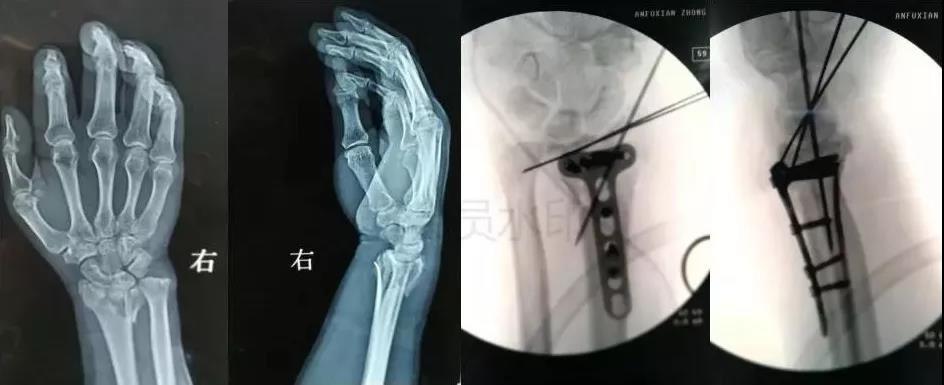

7)手部骨折

- 无论闭合或开放性骨折,均应早期复位内固定。

- 合并神经,血管,肌腱损伤,紧急手术。